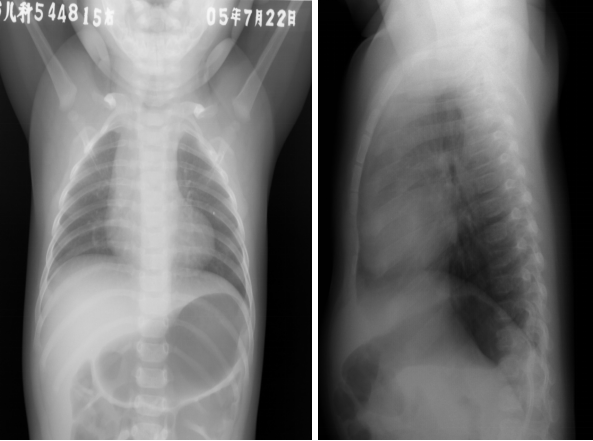

法洛四联症:胸片表现

◇ 心影正常或稍大

◇ “靴形心”:

心尖圆钝上翘,肺动脉段凹陷,上纵膈增宽

◇ 肺野清晰

侧枝丰富者呈网状纹理

◇ 右位主动脉弓(约25%)